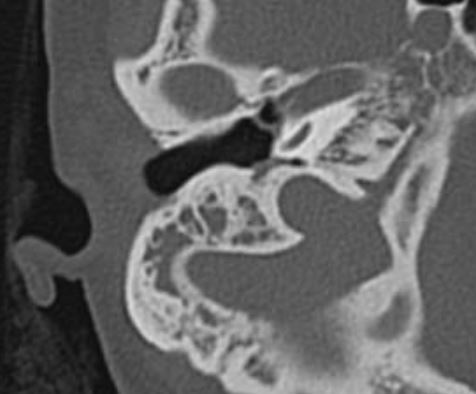

来自广东佛山顺德的刘女士,由于体检发现右侧鼓膜内陷,听力下降,当地医生建议捏鼻子鼓气,但是坚持了几个月没多大效果。最后听说佛山复星禅诚医院耳鼻喉治疗这种情况比较专业。就找到耳鼻喉郑立岗医生,检查后发现李女士是粘连性中耳炎,听力有下降,建议做耳内镜微创手术。

考虑后李女士及时入院了,这次做的是全麻耳内镜粘连性中耳炎微创手术,在耳内镜下不用做任何的体表切口,直接翻起外耳道鼓膜皮瓣,完整翻起内陷的上皮组织后发现听骨链是完整,活动可。取合适大小的耳屏软骨加强鼓膜,整个的手术非常的顺利,持续约60分钟。术后查房患者无明显的不适,无手术相关的并发症。